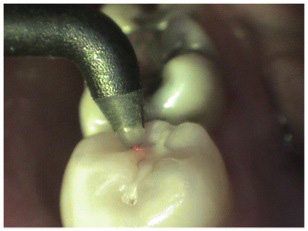

Lasers are devices that use photons of light for benevolent biologic effects. Depending upon the wavelength and the power setting, lasers can be used in a diagnostic fashion such as with the Diagnodent or they can be used in a surgical fashion to be able to gently and precisely cut both hard and soft tissues. The WaterlaseMD is a champion of lasers and performs many different tasks.

WaterLaseMD is our multipurpose laser. It is capable of cutting both hard and soft tissue, as well as many other beneficial biologic effects. This laser can remove a cavity from a tooth, often times without the need for local anesthesia. It is very effective in killing bacteria and is an excellent adjunct to the conventional drill in a deep cavity or preparation. This can be the tipping point between a tooth healing or needing a root canal. There is a secondary healing effect as the laser is being used; the coherent photons of light coming out of the end of the laser are able to penetrate into the pulp of the tooth. The cells in the pulp take up the light and enjoy a biologic effect of healing, reduced inflammation and stimulation of stem cells for repair.

The WaterLaseMD is excellent in soft tissue management. It is commonly used in crown and bridge to trim unhealthy tissue that is necessary to provide a clean impression and healthy post-op healing. Patients are continually amazed at how there is virtually no discomfort, even the next day, after significant amounts of gum have been trimmed. This laser is very effective in other soft tissue applications such as biopsy. Many biopsies can be completed with only the use of topical anesthetic. The WaterlaseMD is also used to sterilize the canals in root canals and is effective in debridement of the sockets of extracted teeth, again killing bacteria and stimulating healing.

Lasers are just photons that are little packets of light that have wide ranging biologic effects. The cells use the laser energy to heal. Surgical lasers are used to treat both hard and soft tissue, The tissue is happy to receive the energy and the remaining healthy tissue heals much faster with less pain. Lasers also kill bacteria and can be used to treat bacterial events such as dental caries and infection. The laser also can be used to drill a tooth is certain situations without the use of local anesthesia. LLLT or Low Level Laser Therapy is a healing laser that stimulates the cells in the area of recent surgeries that helps to decrease pain and speed healing. We also use the Diagnodent which is a Laser Cavity Detector. This painless technology helps to look into a tooth to assess whether a tooth has decay and whether it needs to be restored or not. It is a partner to Minimally Invasive Dentistry where small cavities can be restored in a timely fashion, preserving the future strength and health of a tooth for a lifetime.